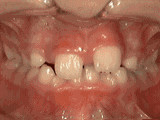

第五种: 开合,即使闭嘴,上下牙齿也不解除,留出空隙,经过矫正后的牙齿是这样的。